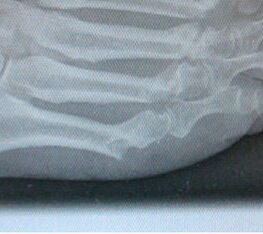

3 mm Inzision dorsal des Metatarsale 5 Köpfchens (Abb. 4). Kapsulotomie und Abheben der Weichteile vom Knochen mit dem Raspatorium (Abb. 5). Eingehen mit der kurzen 2mm Fräse (Abb. 6). Tangentiales Abtragen der Metatarsale 5 Exostose unter dorsoplantarem Schwenken der Fräse. Die Abtragung der Exostose erfolgt unter wiederholter Kontrolle mit dem Bildverstärker (Abb. 7). Nach dem Ausdrücken des pastenartigen Knochenmehls (Abb. 8) wird die Wunde mit einer Knopfkanüle ausgiebig gespült bis das Spülwasser kein Knochenmaterial mehr enthält.

Grundglied Osteotomie: